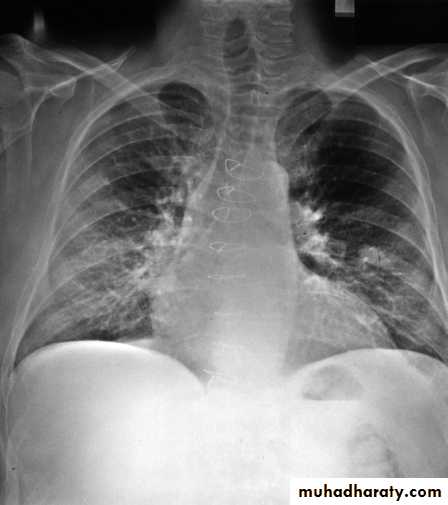

DiseasesPulmonary infection range (Asymptomatic to ARDS)

47-year-old man who underwent orthotopic heart transplantation one year ago has an x-ray showing a right upper lobe pulmonary nodule. The lung biopsy is shown. The most likely diagnosis is C.neoformans